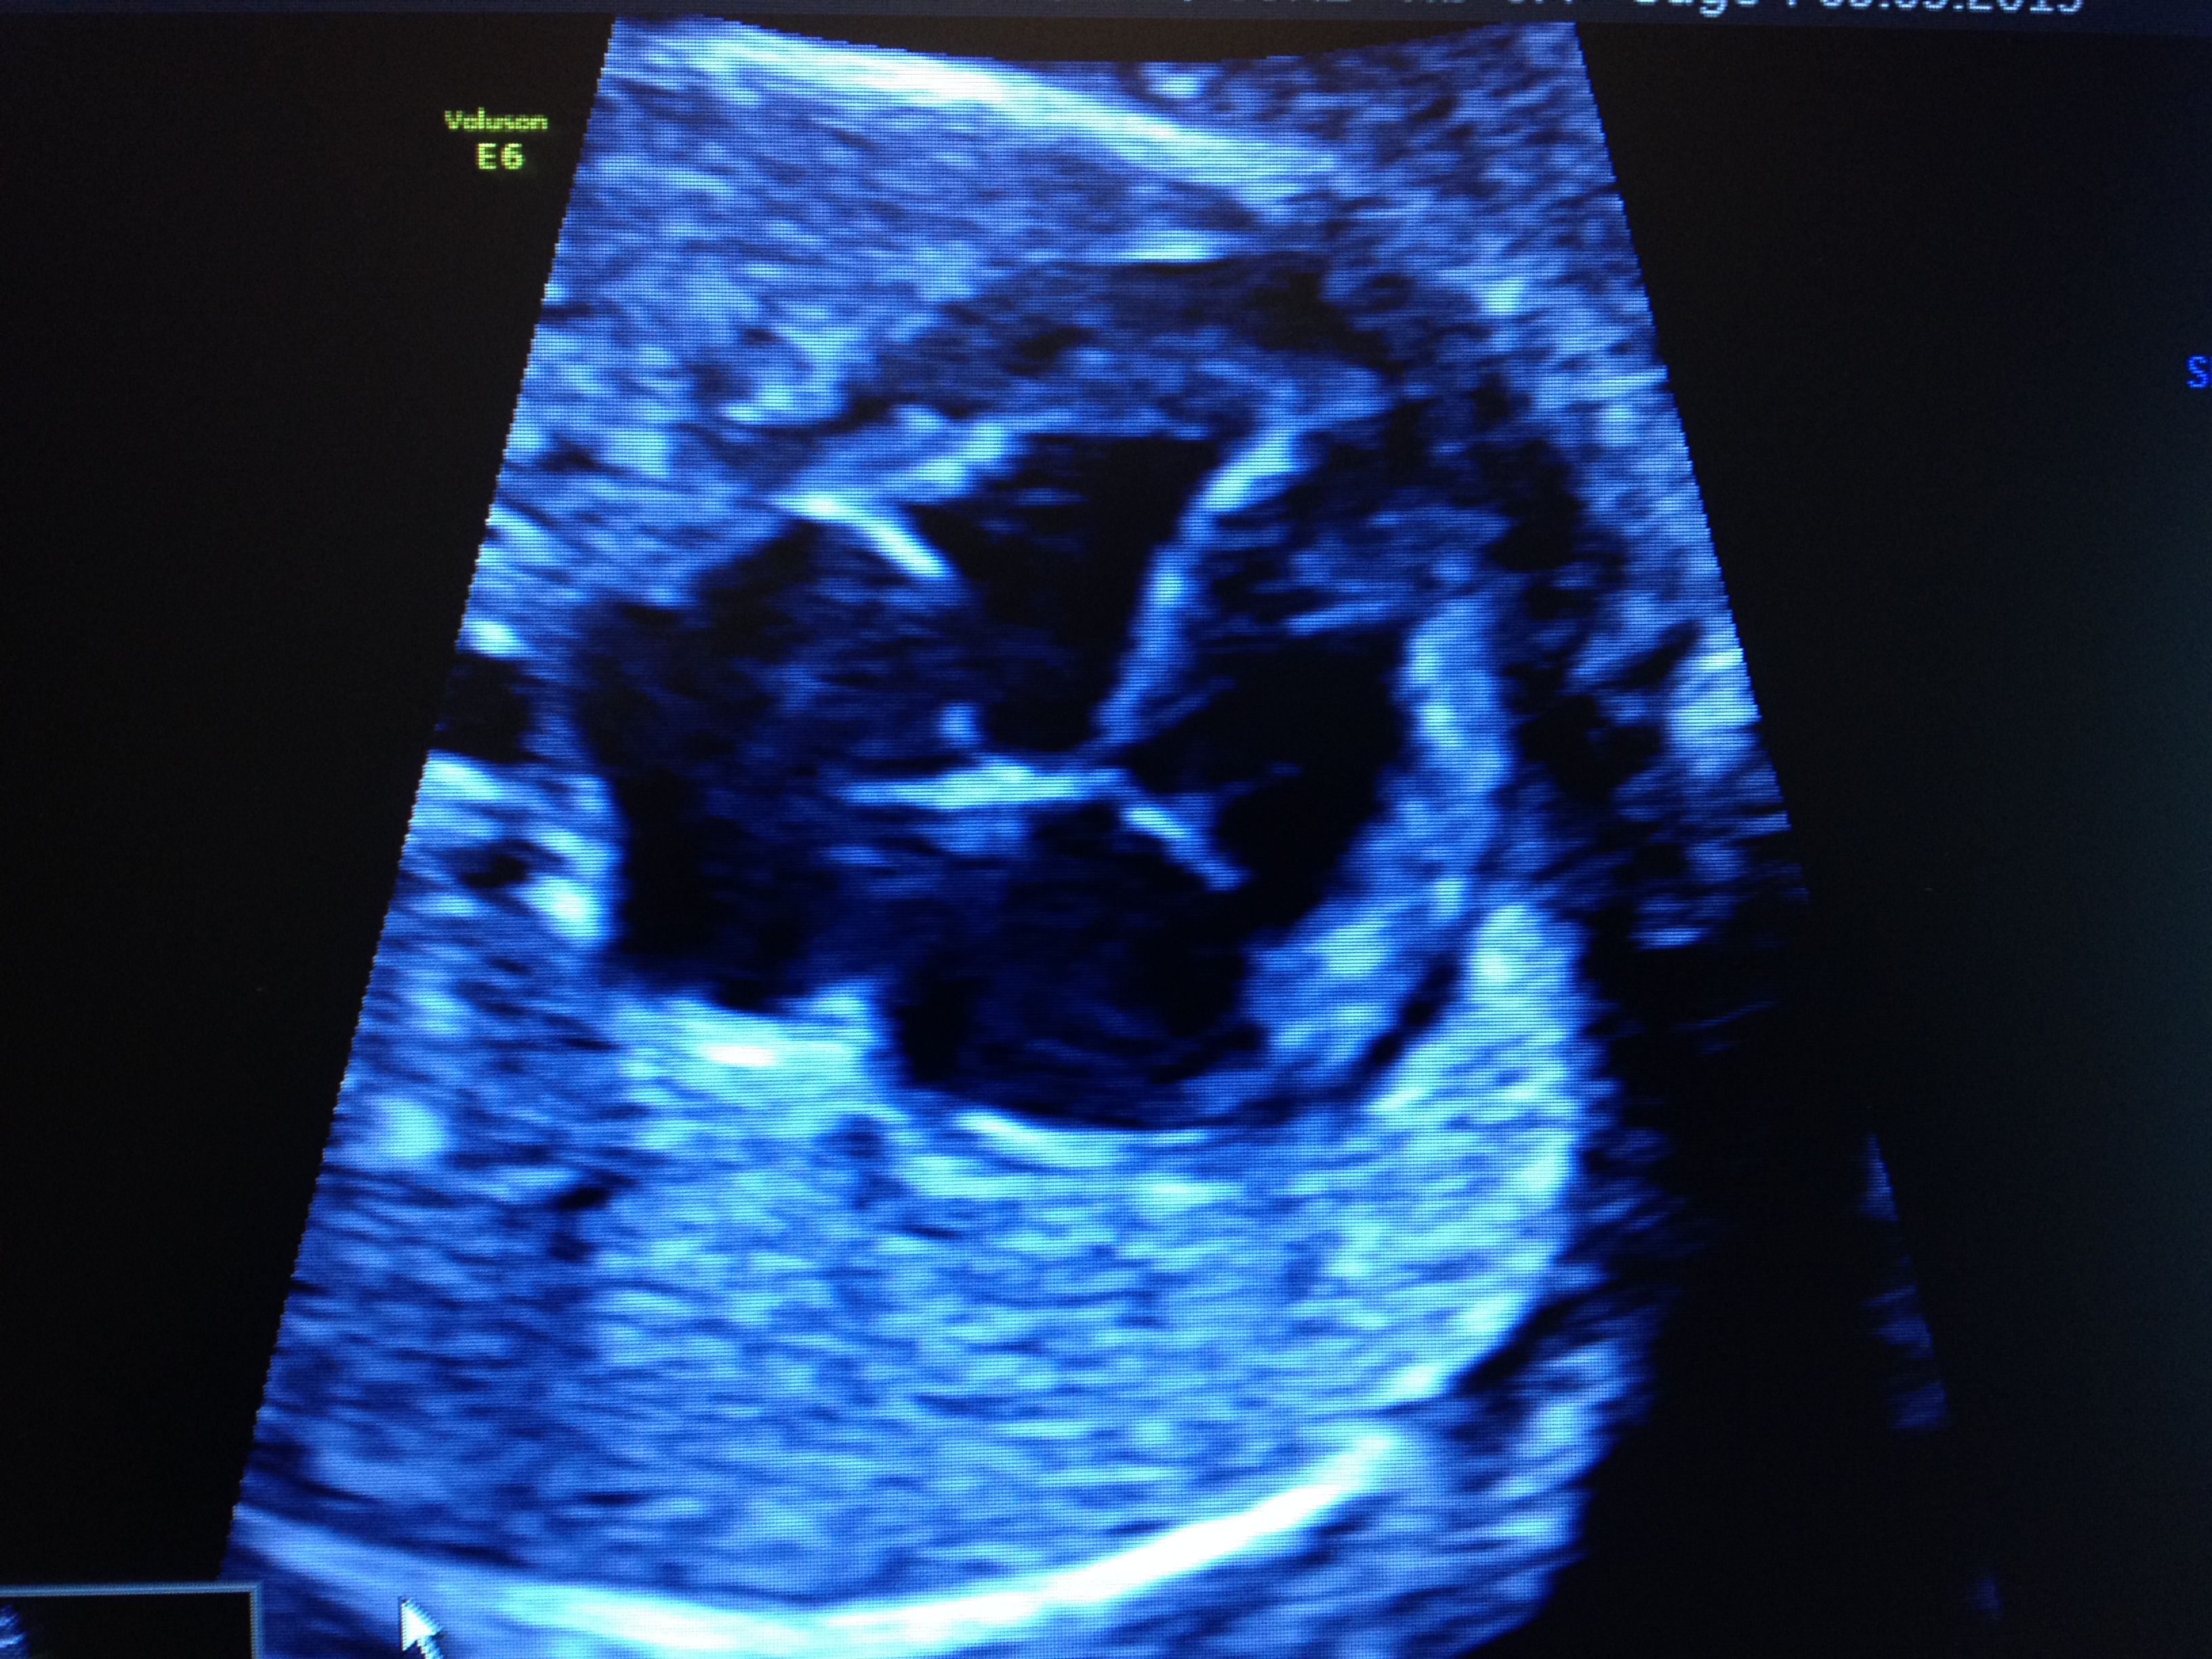

3-Echographie de 32 sa

Elle vérifie la position fœtale en vue de l'accouchement , la bonne croissance du fœtus et contrôle sa morphologie et la position du placenta.